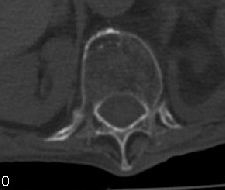

男:89岁因外伤后2天行ct检查。请各位战友讨论图中所指是否是骨折和形成该影像的原因(扫描层面位于椎体中份)。

腰椎退变并骨质疏松

不象骨折,属退行性变

不象骨折,虽然的双边影,但是椎体前后径没有变化,可能只是骨质增生所致

考虑压缩性骨折,腰椎退变并骨质疏松